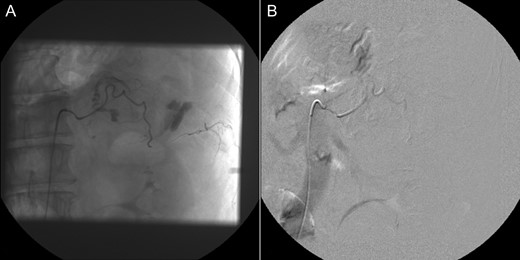

A 60-year-old male presented with pain at the left upper quadrant and left flank, radiating to the back. The patient had known hypertension and had suffered a myocardial infarction a year ago with stent insertion, now being on aspirin and clopidogrel. Upon admission all observations were normal. On examination, tenderness with guarding were noted at the left upper quadrant. Giordano sign was strongly elicited. Laboratory investigations were normal other than leukocytosis (WBC: 15.300, 89% neutrophils). US was unremarkable and CT scan revealed a retroperitoneal hematoma, at the site of the left adrenal gland, associated with extravasation of contrast (Fig. 3). The patient underwent angiography and active bleeding was confirmed from the middle adrenal artery which was successfully embolized microspheres (Fig. 4). The patient was transferred to ICU. He remained hemodynamically stable, without requiring blood transfusion. Four days later he was transferred to the ward. Pheochromocytoma was excluded with VMA, while ACTH and cortisol measurements ruled out adrenal insufficiency. Clopidogrel was permanently discontinued. The patient was discharged after 14 days and follow-up MRI confirmed hematoma resolution excluding an underlying mass.

Case 2 presenting imaging (CT) showing a large left peri-adrenal hematoma.

Selective adrenal artery angiography showing active extravasation from the middle adrenal artery (A) and subsequent successful embolization (B).